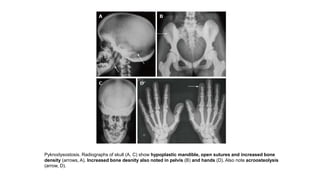

Pyknodysostosis. Radiographs of skull (A, C) show hypoplastic mandible, open sutures and increased bone

density (arrows, A). Increased bone desnity also noted in pelvis (B) and hands (D). Also note acroosteolysis

(arrow, D).